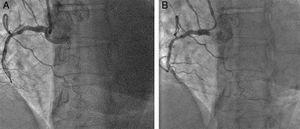

A 69-year-old female with a past medical history of hypertension, dyslipidemia, coronary artery disease and a coronary angioplasty with two drug-eluting stents in the proximal first obtuse marginal artery and the mid-right coronary artery (RCA) 8 years previously presented to our hospital with recurrent angina and was referred for cardiac catheterization. After obtaining informed consent, coronary angiography performed through the TRA revealed an occlusion of the mid-RCA just distal to the previous stent. The distal RCA was observed to backfill following a contralateral injection of the left coronary artery. Therefore, anterograde angioplasty of the RCA CTO was performed from the radial artery using a 6Fr JR guiding catheter that provided poor support, and the occlusion was not successfully crossed (Fig. 1a). Therefore, a 5-in-6Fr Guideliner catheter was passed into the mid-RCA and a Pilot 150 (Abbott Vascular, Santa Clara, California, USA) wire crossed the CTO with a 1.0mm×10mm Falcon CTO (Invatec, Roncadelle, Italy) balloon support (Fig. 1b). Serial predilatations with 1.5mm×15mm and 2.0mm×15mm semi-compliant balloons were performed (Fig. 2a), and a 2.5mm×38mm Xience Xpedition (Abbott Vascular, Santa Clara, California, USA) stent was deployed (Fig. 2b) with a good final angiographic result (Fig. 2c).